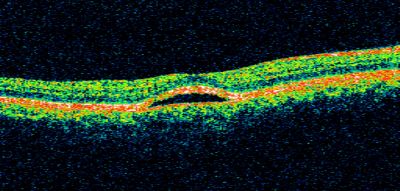

Best Disease, Vitelliform Macular Dystrophy - 6 year old child

VISUAL ACUITY: Vision OD is 20/30, OS is 20/100.